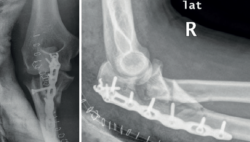

Figura 7. Fractura-luxación variante de Monteggia con desplazamiento posterior. El paciente fue intervenido realizando la fijación del cúbito con una placa posterior y un tornillo adicional desde la cara lateral sin llegar a reducir la fractura de la coronoides y la resección de la cabeza del radio. A la semana de la intervención quirúrgica se observa la luxación posterolateral del antebrazo.